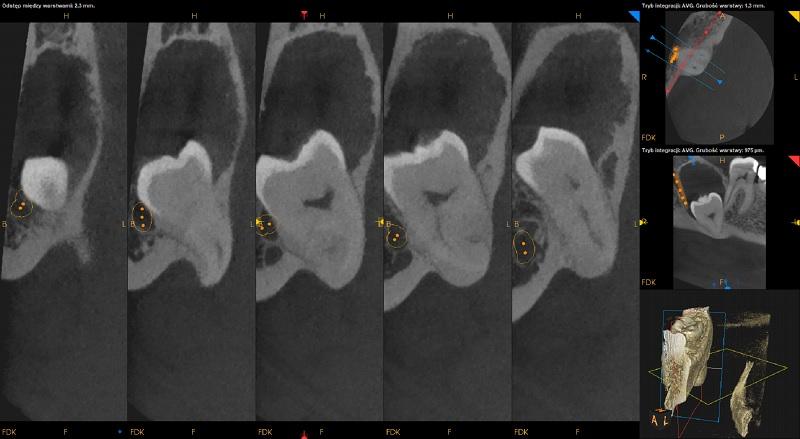

Ząb 48 – zatrzymany. Położony nisko przy dolnej krawędzi żuchwy, pionowo skośnie, koroną skierowany w stronę dystalna i policzkową. Korzenie zagięte. Wierzchołki korzeni uwypuklają się po stronie językowej żuchwy. Kanał nerwu zębodołowego dolnego biegnie po stronie policzkowej zęba 48. Ząb w kontakcie z kanałem. Nad zębem 48 rozległe ognisko osteolityczne obejmujące koronę zęba oraz kanał nerwu zębodołowego dolnego – obraz radiologiczny może odpowiadać rozległej torbieli zawiązkowej okołokoronowej lub rogowaciejąco-torbielowatemu guzowi zębopochodnemu (KCOT).